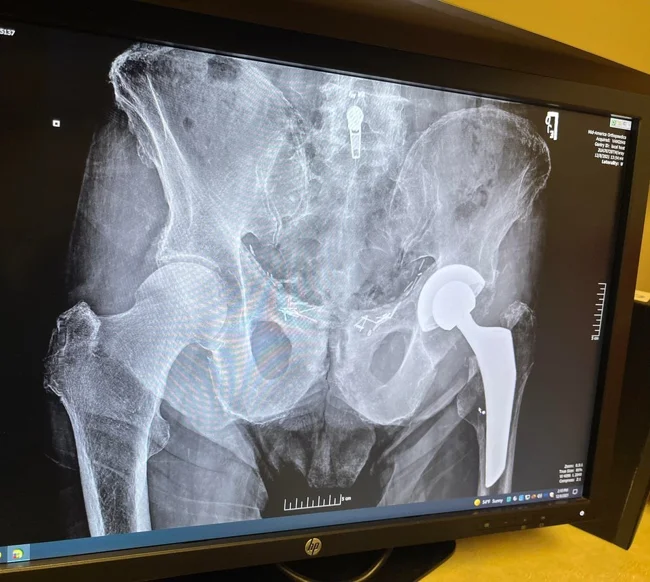

Слева - новое бедро